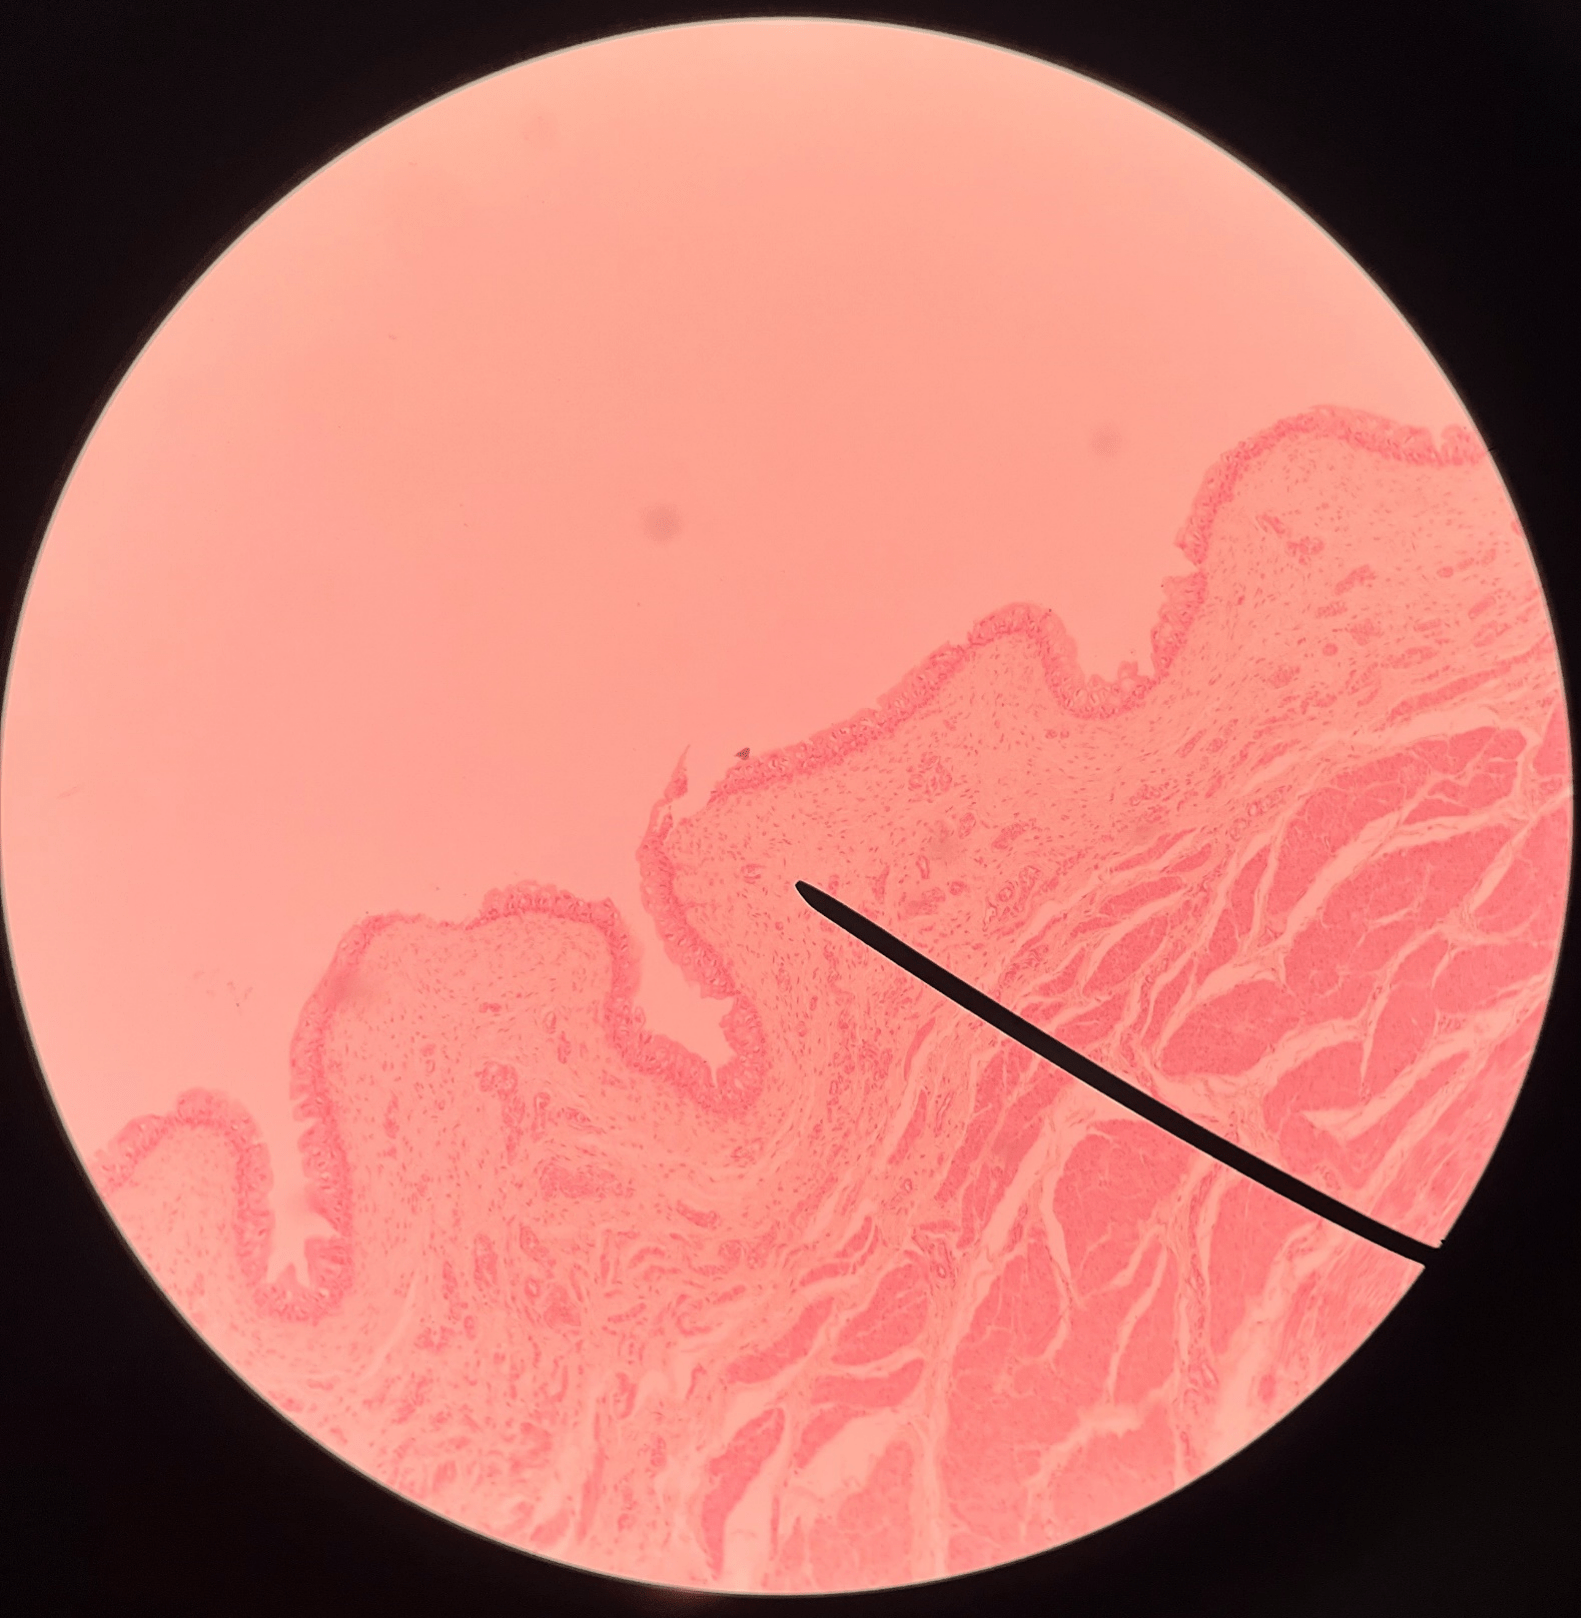

• Slide histology of the ureter.

• The outermost layer of the ureter.

• Composed of connective tissue.

• Superficial to the circular layer of the muscularis.

23

New cards

circular layer of muscularis

• Slide histology of the ureter.

• A smooth muscle layer of the ureter.

• Superficial to the longitudinal layer of the muscularis and deep to the adventitia.

New cards

longitudinal layer of muscularis

• Slide histology of the ureter.

• A smooth muscle layer of the ureter.

• Superficial to the mucosa and deep to the circular layer of the muscularis.

New cards

mucosa

• Slide histology of the ureter.

• The innermost layer of the ureter.

• Composed of urothelium.

• Faces the lumen of the ureter and is deep to the longitudinal layer of the muscularis.